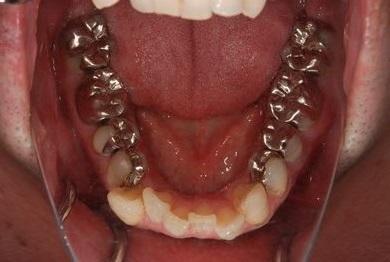

治療前

• 治療前